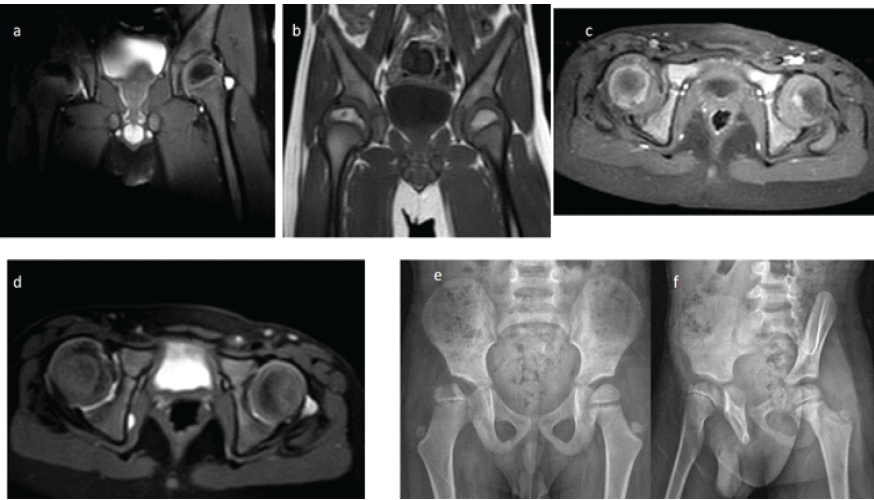

All post-operative radiographs and MRI studies were reviewed to assess acetabular development, femoral head containment, epiphyseal height, and synovial thickness. To minimize observer bias, all quantitative radiologic measurements were independently performed by two authors, and mean values were used for analysis. Furthermore, all MRI examinations were evaluated and confirmed by a musculoskeletal radiology specialist with expertise in pediatric hip imaging. Radiographic evaluation at the 5th post-operative year, including contrast-enhanced MRI and X-rays, revealed regression of the previously observed subchondral cyst in the epiphysis (Fig. 5a,b). The perfusion of the epiphysis remained comparable to the healthy contralateral hip, similar to previous years, and the avascular area did not show any progression on MRI (Fig. 5a, b, c, d). The lateralization of the femoral head, attributed to synovial thickening, remained unchanged without further increase; however, no improvement in synovial thickening was noted either. Compared with the early post-operative X-rays from the 1st year (Fig. 1f), the femoral head demonstrated improved medialization at the 5th post-operative year, evidenced by increased metaphyseal overlap (Fig. 5e and f). The acetabular steepening observed at the 4th post-operative year was no longer present, suggesting a favorable correction in acetabular development.

Figure 5: Radiographic evaluation of the patient at the 5th post-operative year. (a) T2-weighted coronal magnetic resonance (MR) image demonstrating similar signal intensity of the epiphysis, indicating limited necrosis of the right femoral head. (b) T1-weighted coronal MR image showing regression of the previously observed subchondral cyst. (c) Contrast-enhanced axial MR image revealing comparable enhancement patterns, suggestive of similar perfusion in both femoral heads. (d) Short tau inversion recovery axial MR image showing increased synovial tissue thickness on the right side without alteration in acetabular anteversion, indicating preserved acetabular development. (e) Anteroposterior pelvic radiograph demonstrating stable femoral head morphology compared with the previous year, with no increase in lateralization or evidence of acetabular dysplasia. (f) False-profile radiograph showing excellent anterior coverage of the femoral head.

The epiphyseal height ratio (injured/non-injured side), measured on coronal short tau inversion recovery MRI, was 0.86 at post-operative 3 months and 0.89 at post-operative 5 years. These findings indicate that the metaphyseal collapse did not worsen over time, although no substantial improvement was observed either. The medial synovial thickness ratio (injured/non-injured side), measured on coronal images, decreased from 1.53 at post-operative 3 months to 1.17 at post-operative 5 years, demonstrating a clear improvement in medial synovial thickening at the latest follow-up. The Reimer’s migration index, reflecting femoral head containment, was 44.7% at post-operative 3 years and improved to 48.8% and 52.1% at the 4- and 5-year follow-up radiographs, respectively. These values suggest that despite ongoing insufficiency, femoral head coverage gradually improved over time. The AI, used to assess acetabular development, measured 26° bilaterally at post-operative 6 months. At the post-operative 4th year, a developmental delay was noted in the right hip: While the AI of the left hip had improved to 23°, the right hip remained at 26°. By the post-operative 5th year, however, acetabular development in the right hip had accelerated, and both hips demonstrated a normalized AI of 21°, indicating recovery of acetabular growth on the affected side.